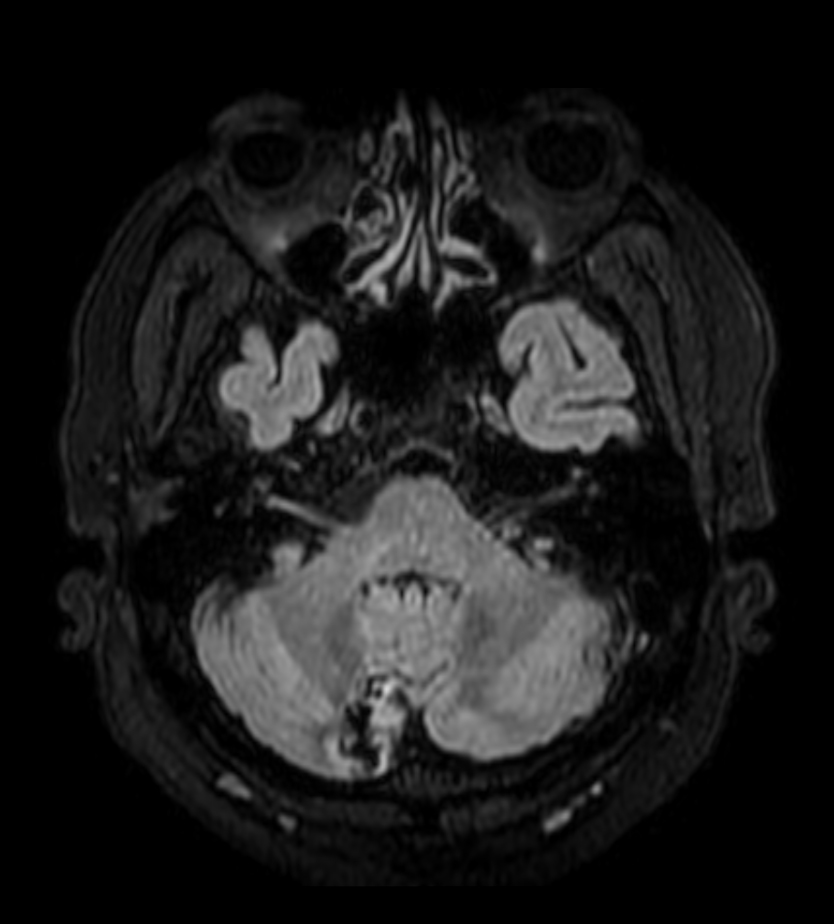

T2w TSE MultiVane XD